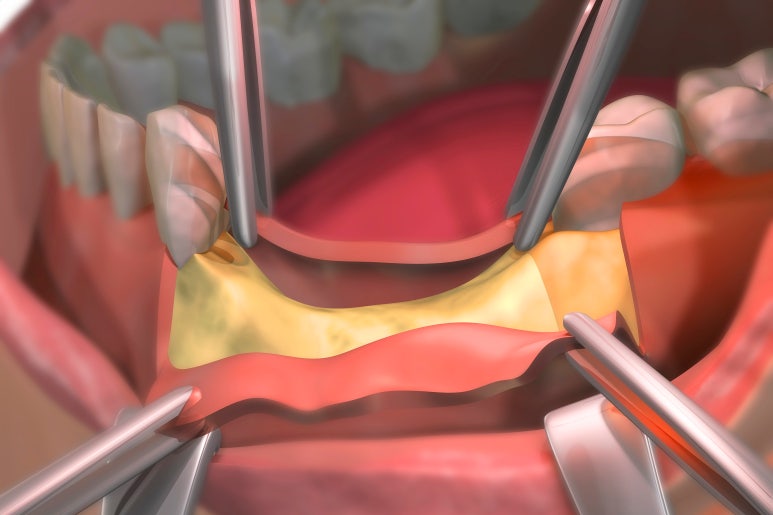

이때 뼈이식은 살 아래쪽에 해야 하므로 뼈이식을 해야 하는 주변 부위를 절개하고 젖힌 다음 골이식재를 넣고 덮게 되는데요.

이 과정에서 당연히 절개 부위는 클 수밖에 없고, 그로 인해 통증과 멍, 붓기 등이 생길 수 있습니다.

어찌 됐든 이 빈 공간에는 '상악동 막'이라고 해서 얇은 막이 씌워져있는데, 이는 마치 달걀의 딱딱한 껍질 내부에 있는 얇은 속껍질과 비슷한 형태입니다.

그래서 막하고 뼈 사이를 벌려서 그곳에 골이식재를 집어넣는 것이 바로 '상악동 거상술'입니다.

따라서 뼈이식을 많이 해야 할 때는 라테랄 어프로치, 즉 옆으로 들어가서 직접 막을 눈으로 보면서 수술하는 것을 고려하게 됩니다.

이때 아무래도 절개 부위가 넓을수록 통증이나 부기, 멍이 들 수밖에 없기 때문에 가능하면 절개를 최소화할 수 있도록 시술자의 노하우와 술기가 필요합니다.